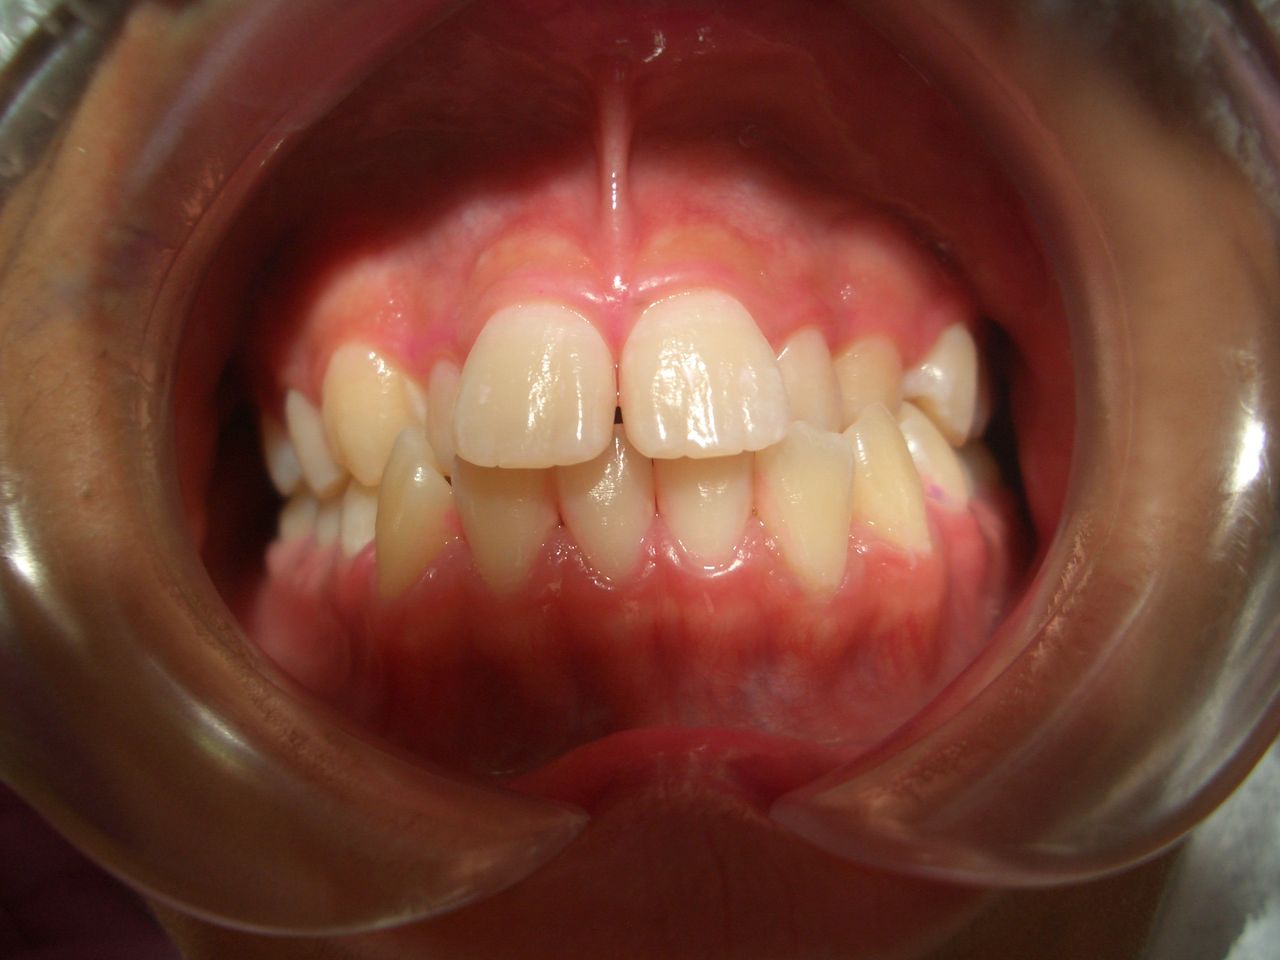

S君の交叉咬合 改善例

S君の非抜歯矯正治療例